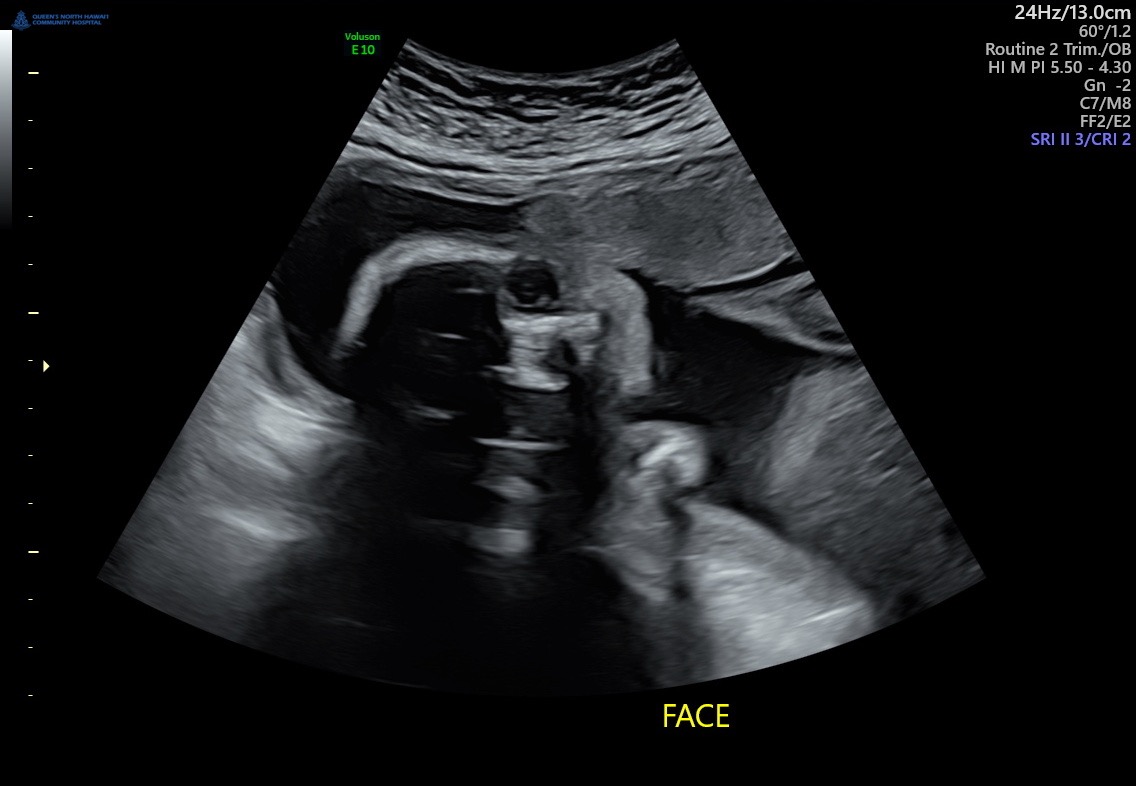

On October 29th, 2025 I walked into a routine 20th week ultrasound but with my excitement put to the side I was taken aback by the way things started taking a turn for the worse throughout the checkup, as I was laying there looking at my beautiful girls growth and admiring her little face when I would get glimpses of her they began the scan of her heart but to my surprise and concern the scan on her heart was taking longer then I remember as I just had a baby 8months ago and have had 3 before I didn’t recall it ever taking this long, my heart began sinking in my chest feeling so powerless and not having my questions answered with certainty was even worse, one ultrasound tech after the other walked in without clear understanding I was sent home with a heavy heart and a lot unanswered what ifs, an appointment was scheduled 2 weeks out to get an echocardiogram for further evaluation, the days couldn’t have gone by any quicker but November 3rd,2025 I walked in to that appointment with hope and faith that things weren’t as they seemed, the tech lays me down explained what she may be looking for and we proceed with the ultrasound she looks at the heart takes a few pictures stops and says there is definitely something wrong with the baby’s heart i am so sorry, let me finish up and I can get into more detail about what’s wrong, instant tears running down my face but keeping it together so she can get what she needs to finish the imaging, she concludes the ultrasound and begins to go more into depth about what she saw feeling weak by the news I get as much information as I can and walk out with a promised call from a pediatric cardiologist on Oahu, patiently waiting I receive the phone call and long story I was told my baby has

HLHS- Hypoplastic Left Heart Syndrom is a complex congenital heart defect where the left side of the heart, including the left ventricle, aorta, and aortic and mitral valves, is underdeveloped. This prevents the left side from properly pumping enough oxygen-rich blood to the body, which is often managed with a series of surgeries, starting shortly after birth. Without intervention, the condition is not survivable.

receiving such crippling news was devastating to me, i got myself together and began my research made appointments necessary so I that we could proceed with this process. I made an appointment for November 21st, 2025 so that I could head up to Oahu to meet the pediatric cardiologist and undergo another echocardiogram to see the progress of baby’s Heart growth, I went up had the echo done and proceeded to go upstairs with the doctor she sits me down and begins to explain the delicate nature of my daughter‘s congenital heart, defect, and what that meant for the remainder of the pregnancy long story short, she explains that I would need to fly off island in order for my daughter to survive after labor and delivery that she would need to undergo three major Hart surgeries with the first and second phase being the most critical and delicate because of infection and downtime to recover the first surgery could take up to nine hours and that between the first and second phase, the hospital would not be able to house us, but it was necessary to stay close for any complications that may occur away from the hospital. Receiving this information really took me back financially emotionally, and physically I wasn’t sure if I was ready, but with my daughter‘s best chances to survive in mind only, I began to make a decision on the hospital. I would be heading out to at around 32 weeks so I could be closely monitored and prepped for labor and delivery where from there I would get very little time with my newborn before she’s taken into the OR